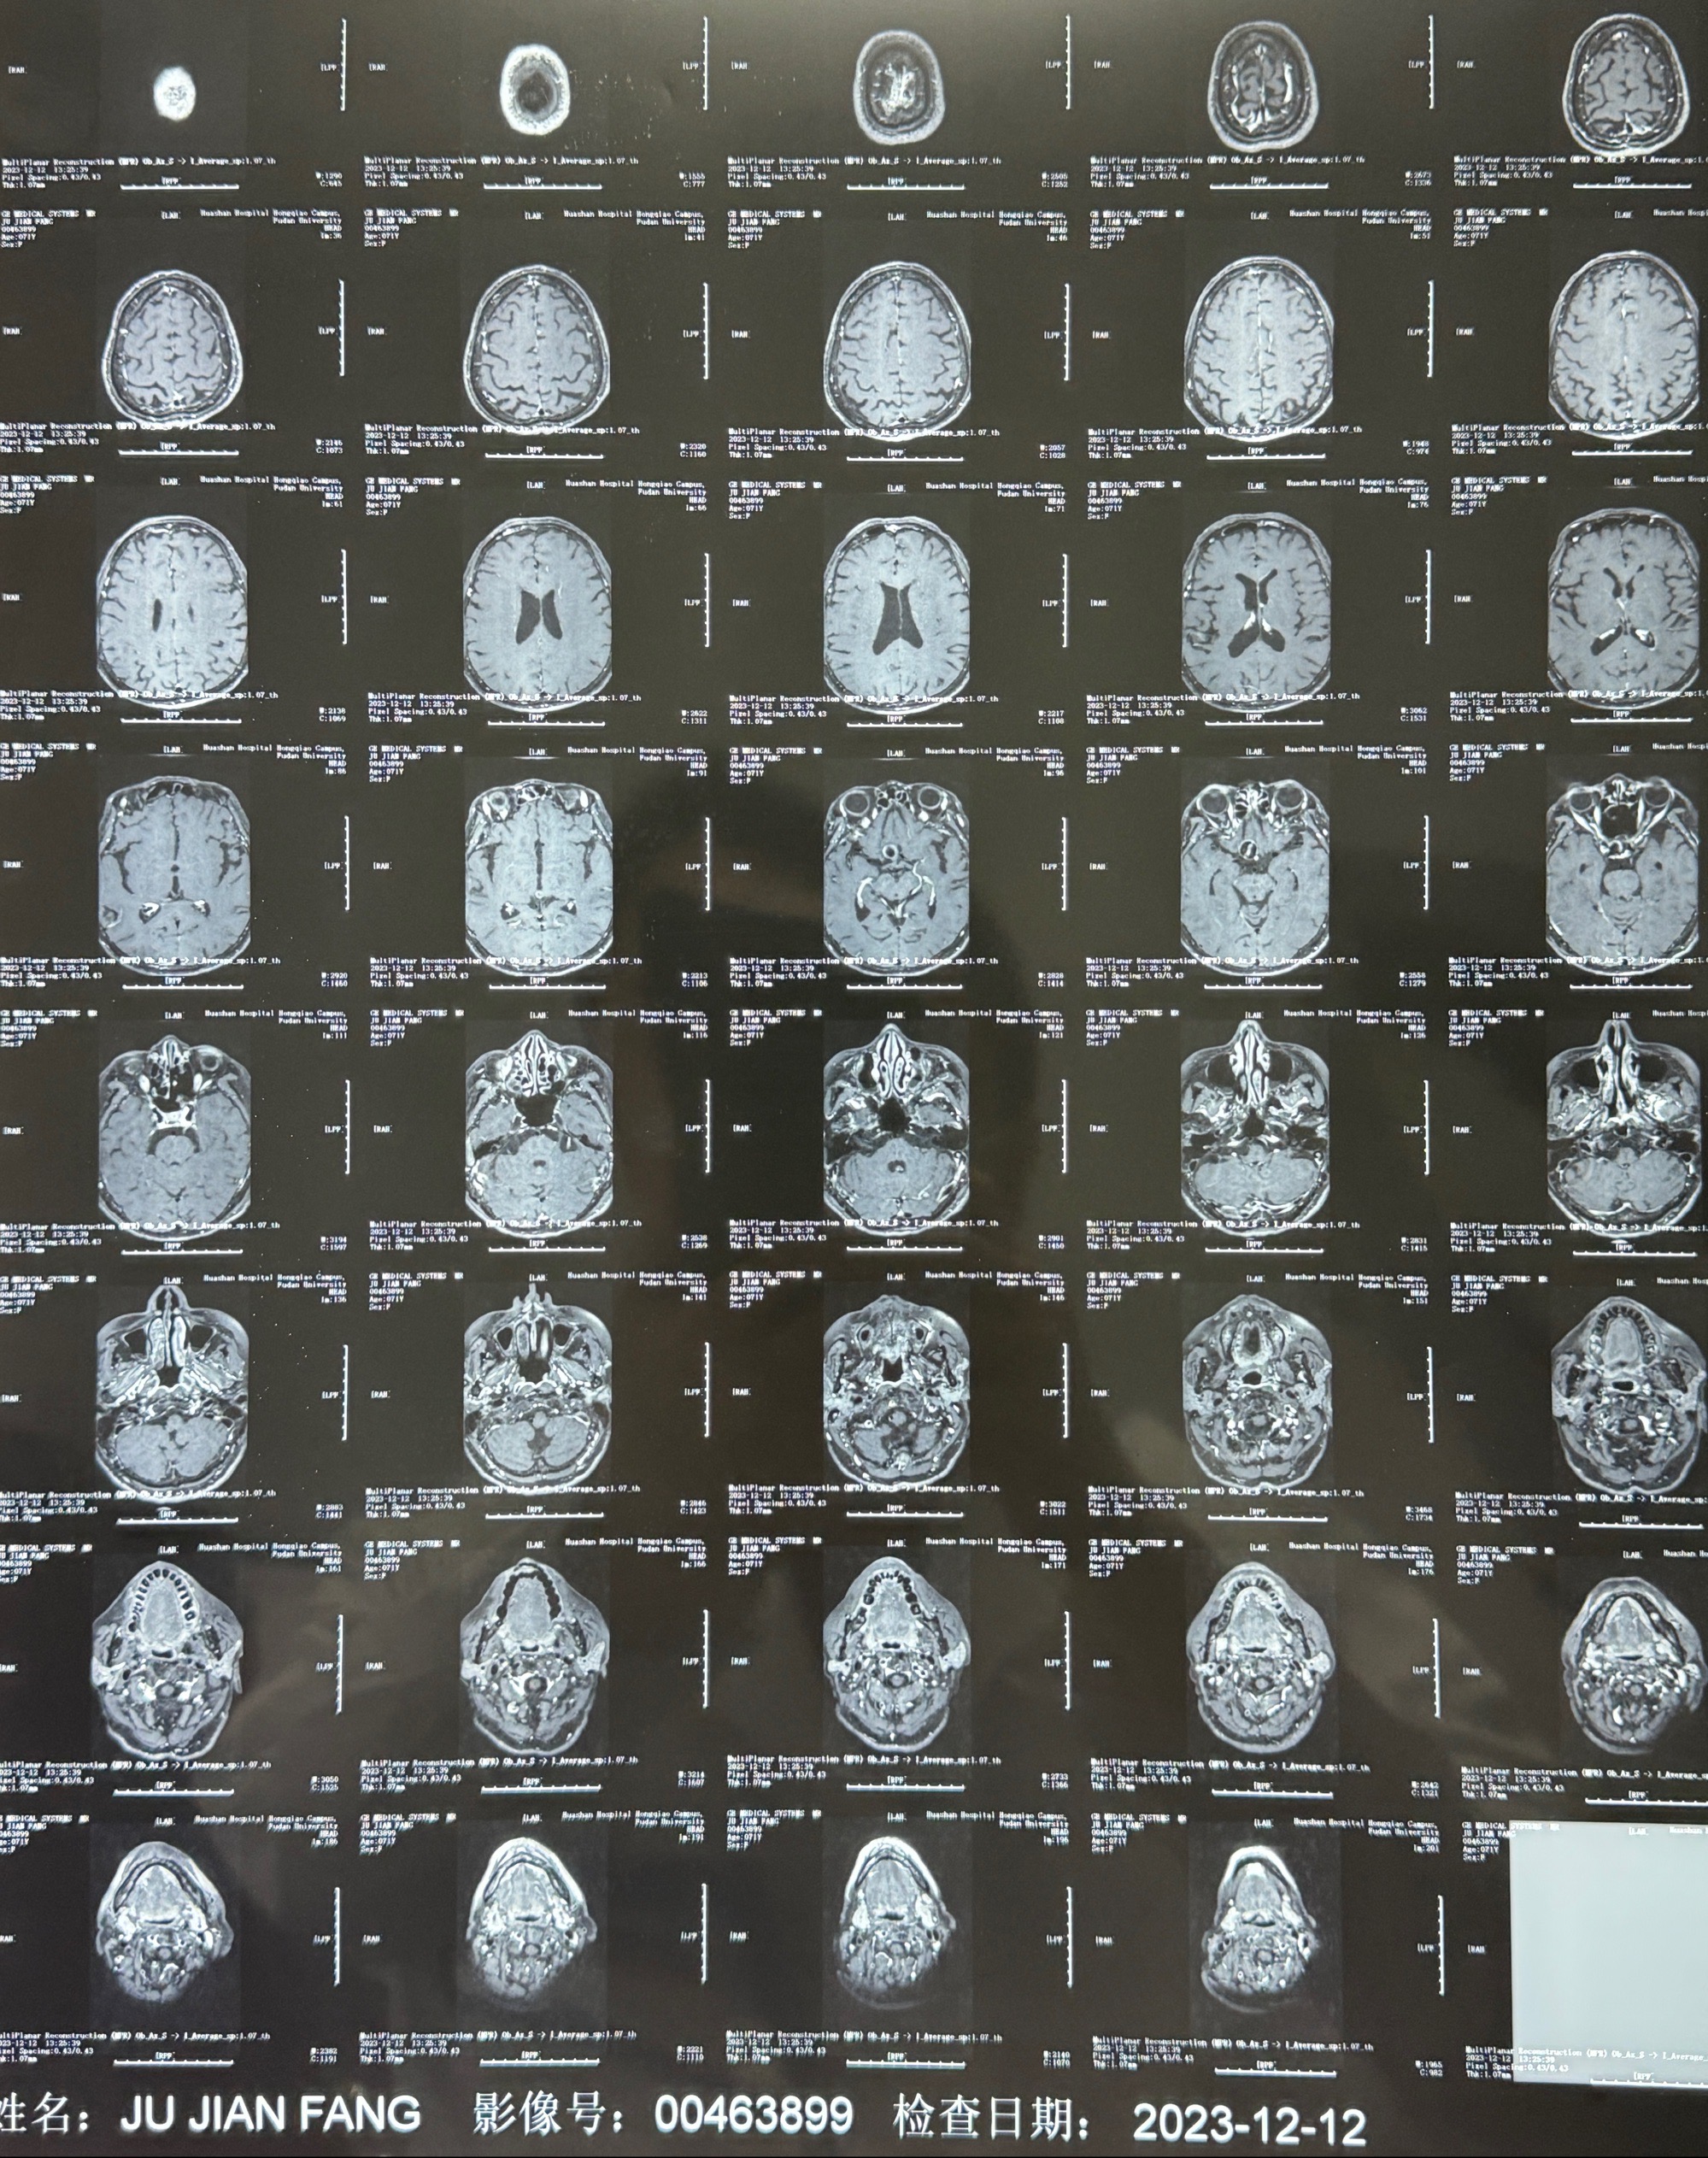

2023-12-12MRI

辅助检查;2023-11 外院 头颅MRI+MRA:左侧颈内动脉C6段动脉瘤;

现病史:患者诉2年来反复发作性头痛,顶枕部为主,因自己考虑高血压可能,未予系统检查;患者约20日前无明显诱因下突发剧烈头晕,有天旋地转感,不能睁眼,伴视物模糊;外院查头颅MRI+MRA提示:左侧颈内动脉C6段动脉瘤;遂至复旦大学附属华山医院就诊,于2023-12-08行全脑血管造影提示:右侧颈内动脉C6段动脉瘤,瘤颈6.68mm,动脉瘤大小13.28*12.34mm,建议行密网支架辅助栓塞术治疗,因缺乏相关材料遂出院。现患者仍有顶枕部头痛不适,为求进一步诊疗脑血管病变至我科就诊,收治入院。